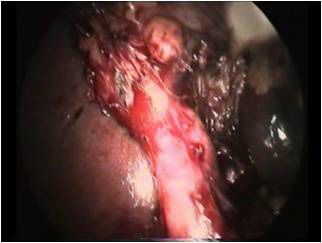

Профилактика такого механизма повреждения заключается в тщательной препаровке зоны впадения пузырного протока в желчный пузырь. Манипуляцию следует начинать у шейки пузыря и продолжать вниз и по задней его стенке, отделяя пузырь от ложа. При этом клипируются и пересекаются пузырные сосуды, формируется окно, образованное задней стенкой шейки пузыря, пузырным протоком и ложем. В ряде случаев мы выделяли практически весь пузырь не пересекая протока. Тщательное отделение пузыря позволяет во время обнаружить подтянутый общий желчный проток и избежать конфликта с ним. Такую диссекцию мы называем прием «хобота» (фото.2). При малейшем подозрении на нетипичную анатомию протоков, производим ИОХГ.

![]() |

| Фото.2. Приём "хобота" |